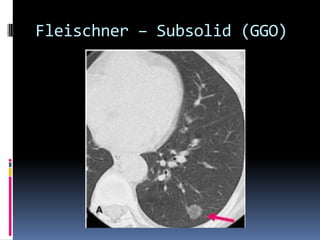

Fleischner – Subsolid (GGO)

Subsolid nodules

 Ground glass (subsolid) nodules are less

dense than solid nodules and the surrounding

pulmonary vasculature and do not obscure

the lung parenchyma.

 Can be purely ground-glass in appearance or

can have mixed solid and ground-glass

components.

 Dilemma: morphologic characteristics of a

ground-glass nodule are less well described.

GGO turns solid - cancer